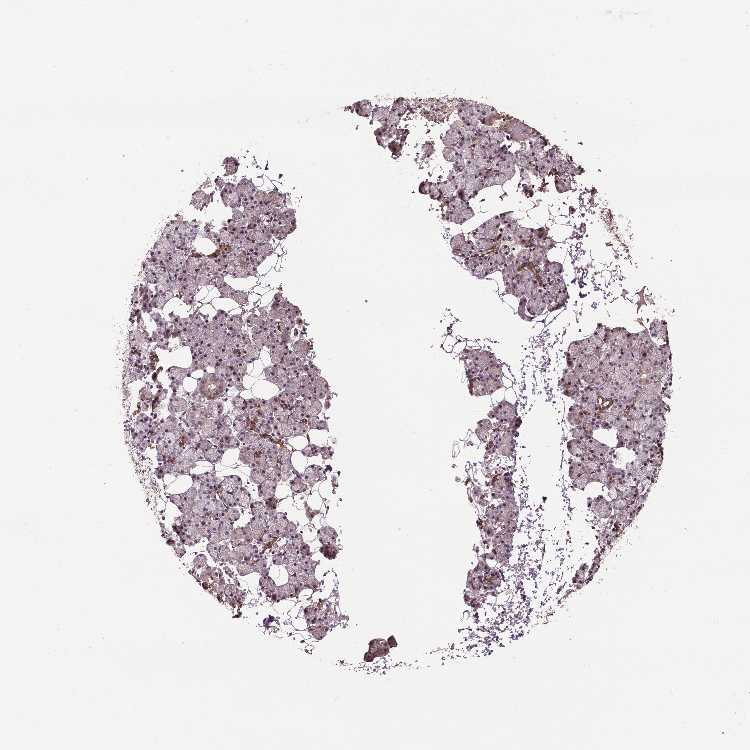

SALIVARY GLAND - Antibody stainingi

Antibody staining in the annotated cell types in the current human tissue is reported as not detected, low, medium, or high, based on conventional immunohistochemistry profiling in selected tissues. This score is based on the combination of the staining intensity and fraction of stained cells.

Each image is clickable and will lead to virtual microscopy that enables deeper exploration of all samples and also displays staining intensity scores, fraction scores and subcellular localization as well as patient and tissue information for each sample.

Antibody CAB070422

Glandular cells Medium